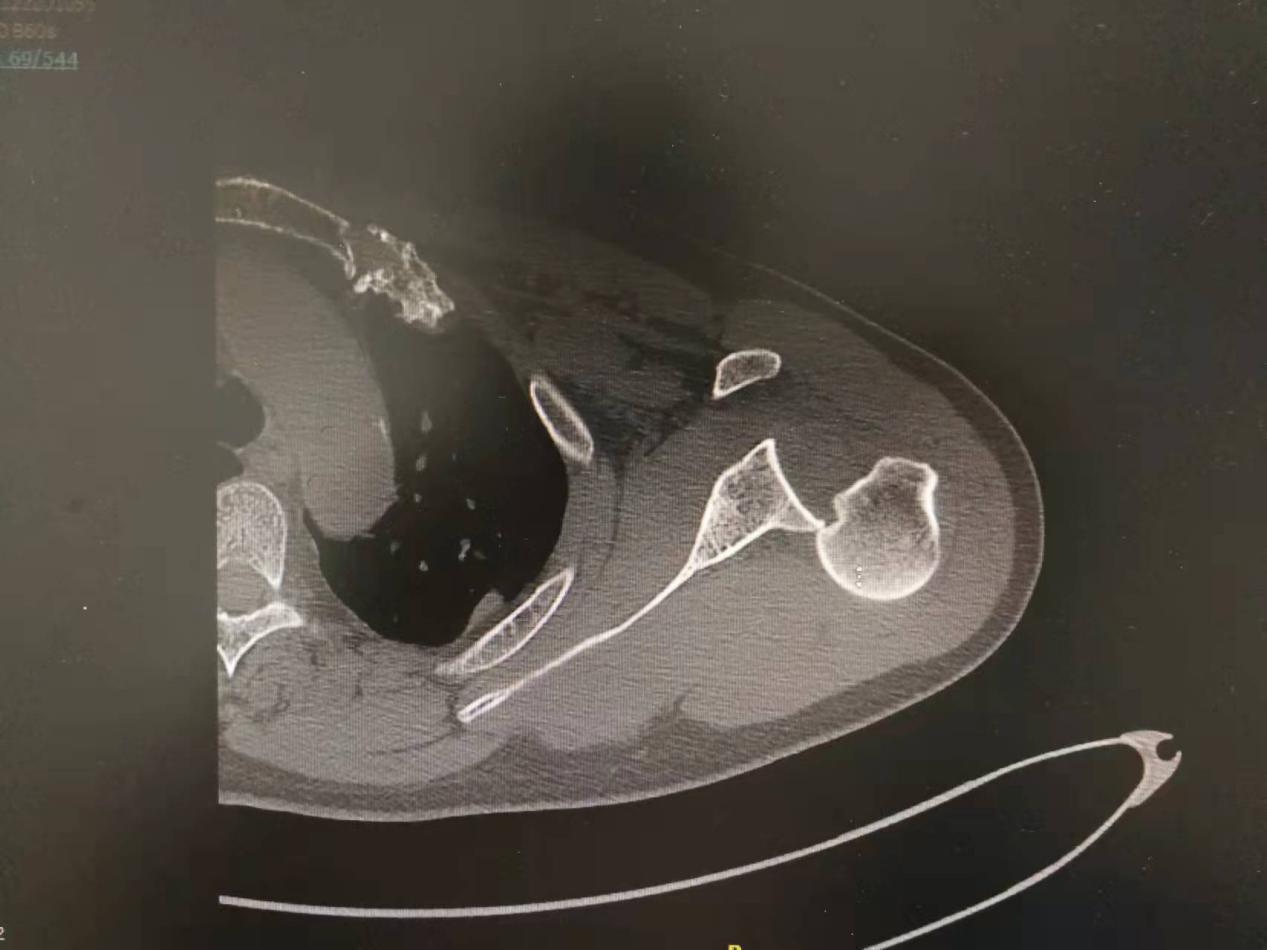

但是患者肩关节仍疼痛明显,入住兰陵县人民医院后,医生给予重新拍左肩关节正位片,症状比入院前明显了,“灯泡征”出现了,显示后脱位;经过CT/MRI的进一步证实,确定是后脱位。

2、仅依赖肩关节正位X线片。肩关节正位X线片“肩胛盂空虚征”缺乏特异性,非诊断肩关节后脱位的可靠表现。肩关节正位片具有“灯泡征”时,一定要给予肩关节X线腋位片及肩胛骨侧位片、CT更加可靠。